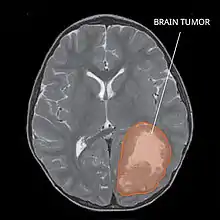

| Primitive neuroectodermal tumor of the central nervous system in a 5-year-old |